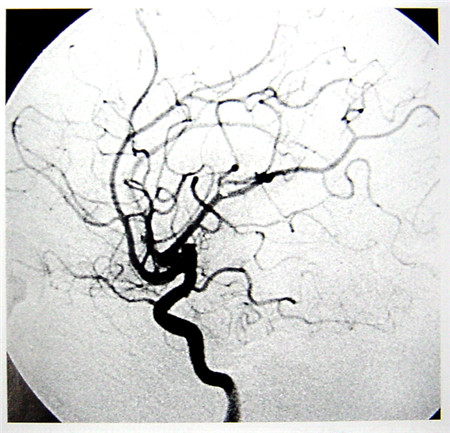

數(shù)字減影血管造影(DSA)簡(jiǎn)介

數(shù)字減影血管造影技術(shù)(Digital Subtraction Angiography,DSA)是一種新的X線成像系統(tǒng),是常規(guī)血管造影術(shù)和電子計(jì)算機(jī)圖像處理技術(shù)相結(jié)合的產(chǎn)物。DSA的成像基本原理是將受檢部位沒有注入造影劑和注入造影劑后的血管造影X線熒光圖像,分別經(jīng)影像增強(qiáng)器增益后,再用高分辨率的電視攝像管掃描,將圖像分割成許多的小方格,做成矩陣化,形成由小方格中的像素所組成的視頻圖像,經(jīng)對(duì)數(shù)增幅和模/數(shù)轉(zhuǎn)換為不同數(shù)值的數(shù)字,形成數(shù)字圖像并分別存儲(chǔ)起來,然后輸入電子計(jì)算機(jī)處理并將兩幅圖像的數(shù)字信息相減,獲得的不同數(shù)值的差值信號(hào),再經(jīng)對(duì)比度增強(qiáng)和數(shù)/模轉(zhuǎn)換成普通的模擬信號(hào),獲得了去除骨骼、肌肉和其它軟組織,只留下單純血管影像的減影圖像,通過顯示器顯示出來。通過DSA處理的圖像,使血管的影像更為清晰,在進(jìn)行介入手術(shù)時(shí)更為安全。

數(shù)字減影血管造影DSA腦血管圖像顯示 核磁共振MRI掃描腦組織圖像